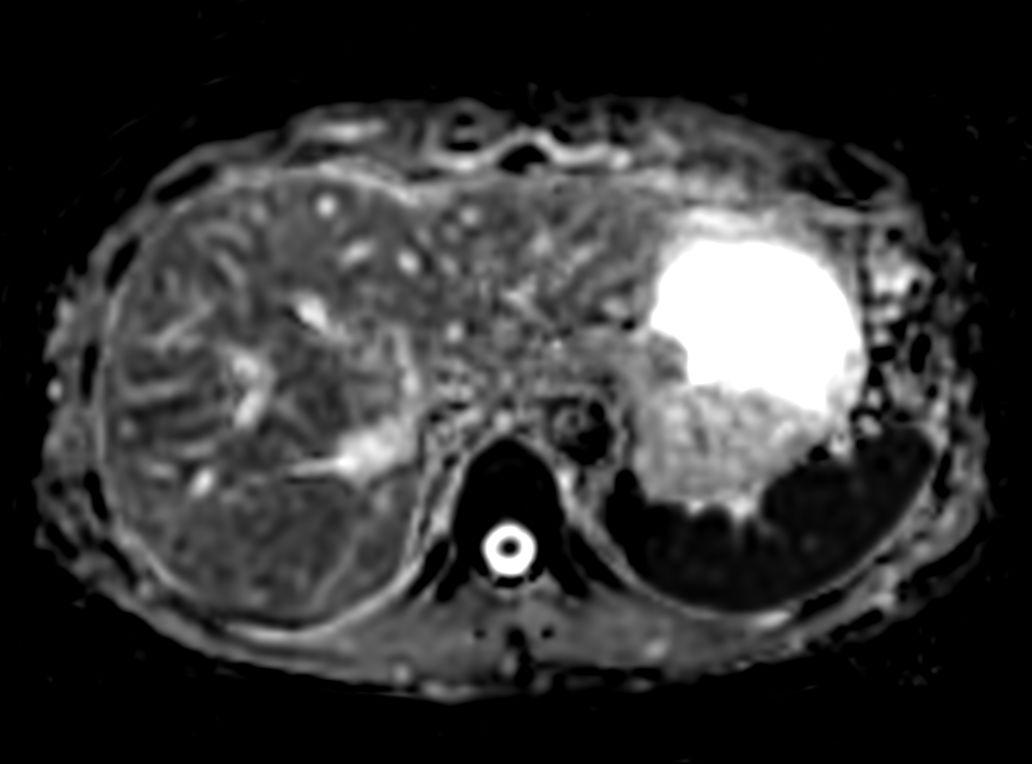

Axial Diffusion (b600)